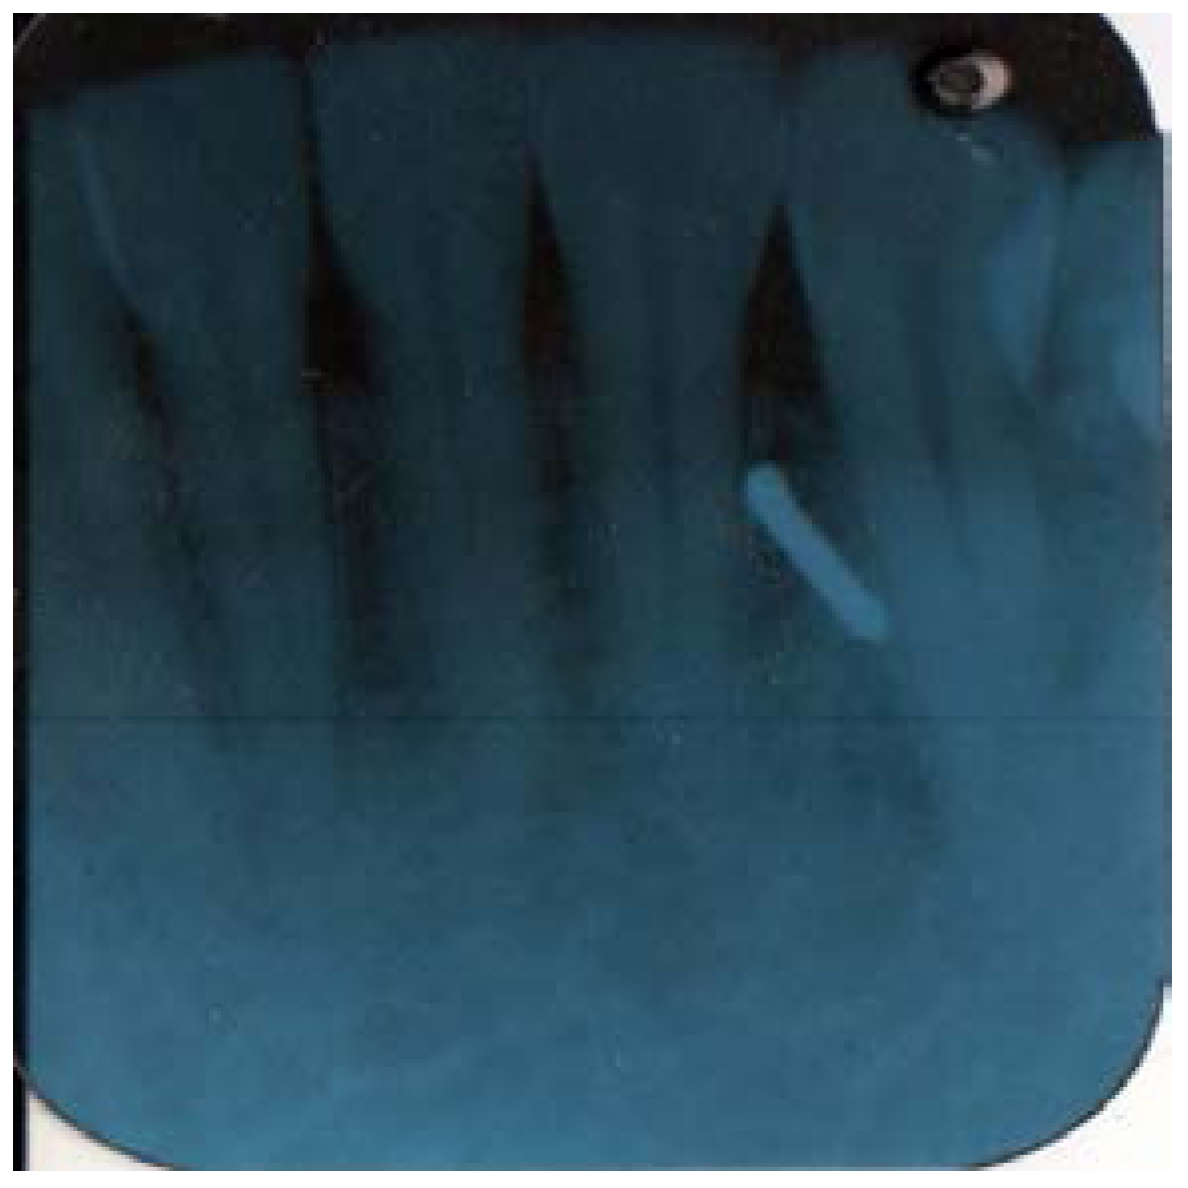

Later in the day, the dentist felt a slight hardness and slight pain upon palpitating the area. By the next day, the swelling had progressed slightly and the dentist felt a slight pain upon palpitation or any movement, such as chewing Figure 1 and Figure 2. He did not think that the small piece of bur was lodged in his chin. A decision was made to have radiographs taken, which included a panoramic and a peri-apical radiograph. Subsequent review of the radiographs revealed a radiopaque image consistent with a broken piece of the bur in the soft tissue of his chin, in the vestibule of the mandibular anterior left side Figure 3 and Figure 4.

Figure 4.

Pri-apical X-ray.